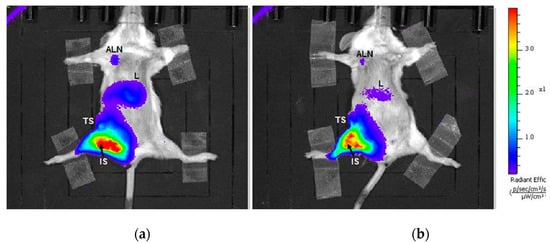

2.4. Lymph Nodes on Tumor Site Showed Markedly Higher Fluorescence In Vivo Then Other Lymph Nodes

2.5. Ex Vivo Fluorescence Signal from Internal Organs Decreased Progressively over Time